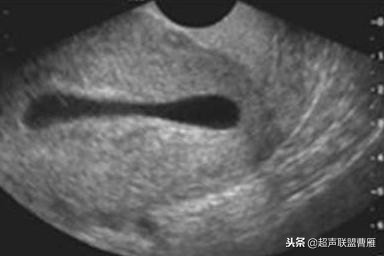

有的图像卵黄囊YS只是两条平行的细短线

妊娠40天,见到卵黄囊、胚极及心管搏动, HCG12800U/L。

妊娠35天,高分辨的超声检查就可能见到心管搏动、胚极及卵黄囊。

卵黄囊高分辨超声图像,妊娠40天